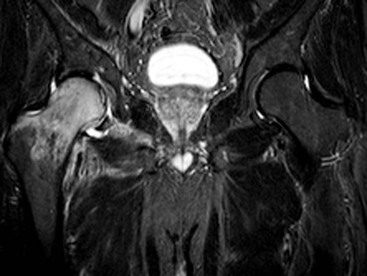

Ischiofemoral impingement is a recently described condition predominantly affecting women associated with narrowing of the space between the ischial tuberosity and lesser trochanter of the femur. It is thought that the quadratus femoris muscle which passes through this space may be impinged during repetitive hip movement, giving rise to pain. MRI reveals narrowing of the space associated with oedema of the quadratus femoris muscle belly and adjacent free fluid (Fig. 46-40).26 However, similar appearances may be found in asymptomatic individuals and the clinical significance of this has not yet been established.